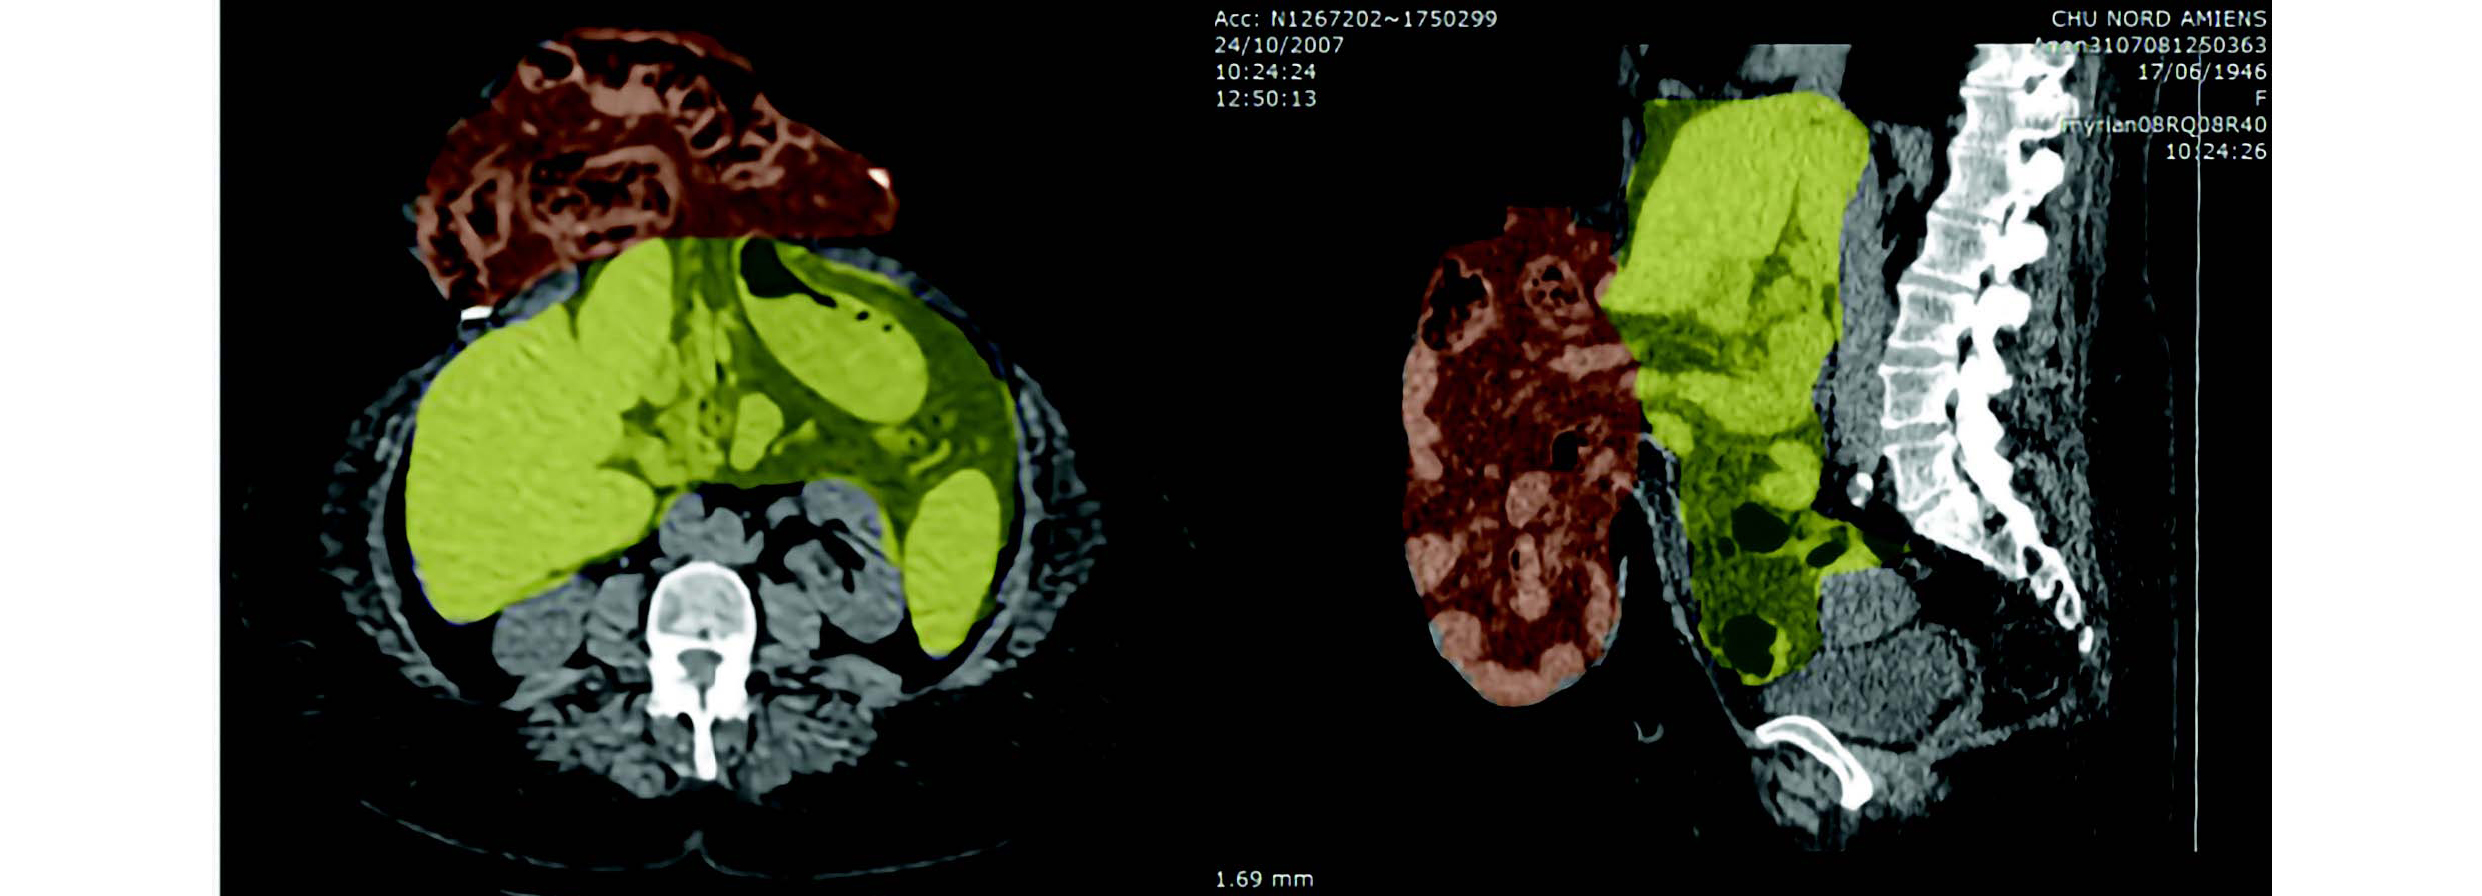

Figure 2 Analyse volume intra-péritonéal après insufflation d'un pneumopéritoine progressif VP = VAC + VIH

Le ratio du volume de l'éventration / volume péritonéal = 4802/(9278+4802) = 34 % C. Sabbagh et al., « Peritoneal Volume Is Predictive of Tension-Free Fascia Closure of Large Incisional Hernias with Loss of Domain: A Prospective Study », Hernia 15, no 5 (1 octobre 2011): 559-65, https://doi.org/10.1007/s10029-011-0832-y.

Historiquement, ces techniques de mesures volumétriques ont été décrites par Tanaka9, qui a donné une méthode simple et rapide de calculs volumétriques, mais qui ne donne qu'une approximation des volumes réels. En 2012, Sabbagh4 décrit une méthode plus précise mais radiologue dépendant. À Rouen, nous utilisons donc la méthode développée par Martre10, basée sur le logiciel Open Source 3D Slicer, avec possibilité de reconstructions 3D. Elle a l'avantage de pouvoir être réalisée par un chirurgien. Elle est rapide et précise, en évitant l'utilisation d'une formule, et permettant ainsi de s'adapter aux éventrations aux formes complexes.

Figure 3 Mesures volumétriques et reconstruction 3D d'une éventration géante avec perte de droit de cité. Ici, volume éventration (2053) / volume péritonéal (11259) = 0,209 = 20,9 % P. Martre et al., « New, Simple and Reliable Volumetric Calculation Technique in Incisional Hernias with Loss of Domain », Hernia 24, no 2 (avril 2020): 403-9